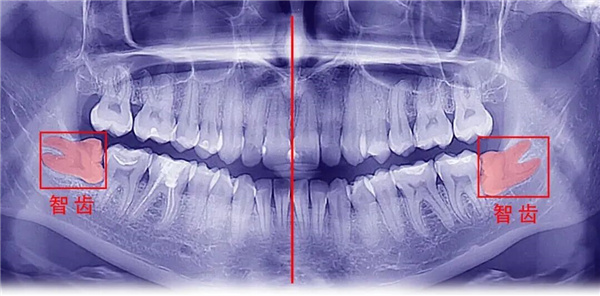

如何初步判断自己是否长智齿?一个简单的自测方法:对着镜子,张大嘴。

以正中门牙缝为中线,向一侧数起。如果你能数到第8颗牙齿,那么这最后一颗就是智齿。

如果数不到,也不代表没有,它可能还完全埋在牙槽骨内(即“埋伏阻生”),需要通过口腔齿光片(如全景片)才能明确诊断。